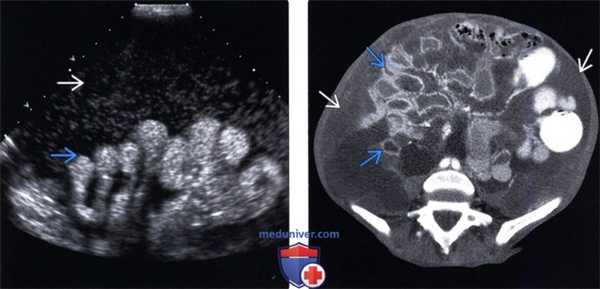

(Левый) Пациент, перенесший две трансплантации почки, с жалобами на вздутие живота. На поперечном УЗ срезе левого фланка определяется подвижная неосумкованная асцитическая жидкость, содержащая источники низкоинтенсивных эхосигналов.

(Правый) У этого же пациента при диагностическом парацентезе получена жидкость молочного цвета, что соответствует картине хилезного асцита. Диагноз подтверждается анализом на уровень триглицеридов в асцитической жидкости.

(Левый) Пациент с псевдомиксом ой брюшины на фоне муцинозной карциномы червеобразного отростка. Жидкость в полости брюшины содержит множественные неподвижные источники низкоинтенсивных эхо-сигналов. Прилегающая кишка смещена кзади.

(Правый) При КТ с контрастным усилением на аксиальной томограмме у этого же пациента определяется осумкованная муцинозная жидкость низкой плотности, смещающая и сдавливающая кишку.